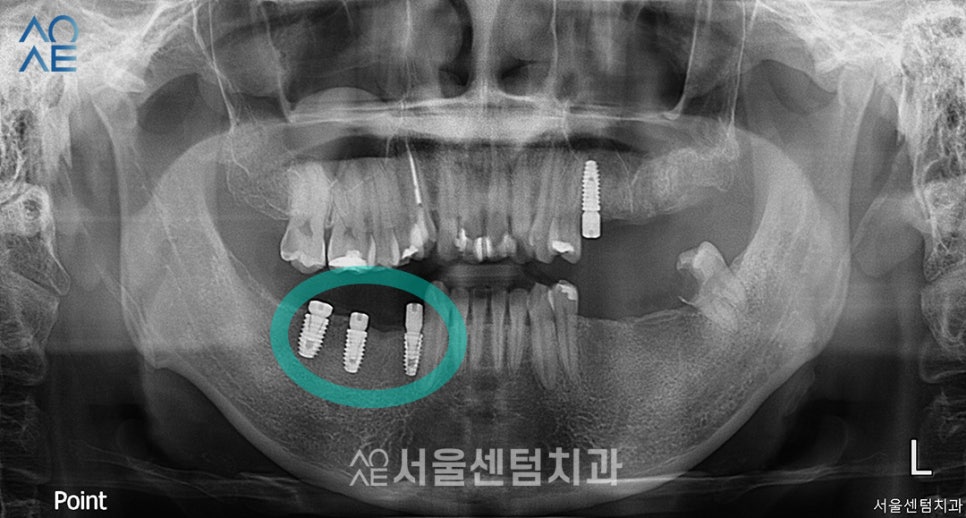

발치 후 잇몸이 아물고나서는

그 옆 어금니 임플란트도 식립하였습니다.

역시나 일체형으로 진행하였고

이렇게 아랫니는 총 5개를 식립하게 되었습니다.

먼저 식립한 오른쪽 부분의 잇몸은 잘 아물어서

바로 보철물 제작도 들어가기로 했습니다.